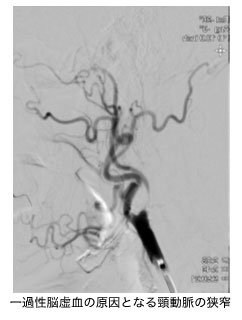

手足がしびれたり、麻痺したりすることは、日常生活の中でも比較的よく起こります。長時間正座して血液の流れが悪くなり、一時的にしびれるケースもありますが、この場合は特に問題は生じません。しかし、脳や脊髄などの神経に原因があるケース、糖尿病などの生活習慣病によって引き起こされるケースもありますので、原因を突き止めることが重要となります。脳神経外科・内科では、こうしたしびれや麻痺の原因をできる限り絞り込み、脳・脊髄・末梢神経など、神経の異常が原因で起こってくるタイプの疾患について治療を行います。